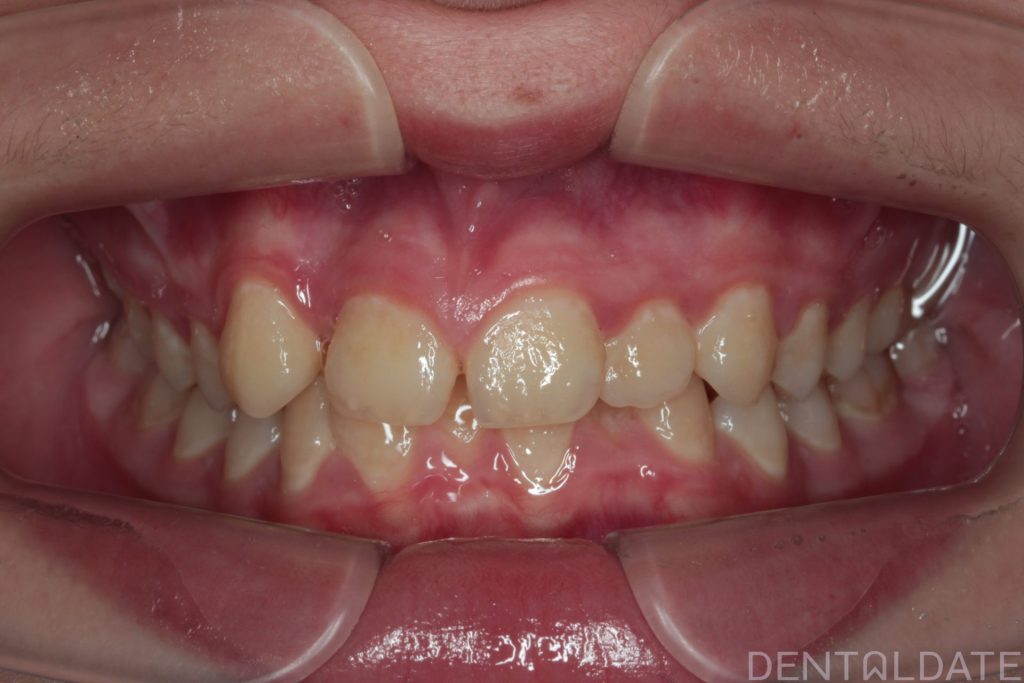

The patient presented with a complaint about an unattractive smile.

One tooth had erupted palatelly, with no space available for it in the dental arch.

The central aesthetic lines did not match, and the bite was incorrect.